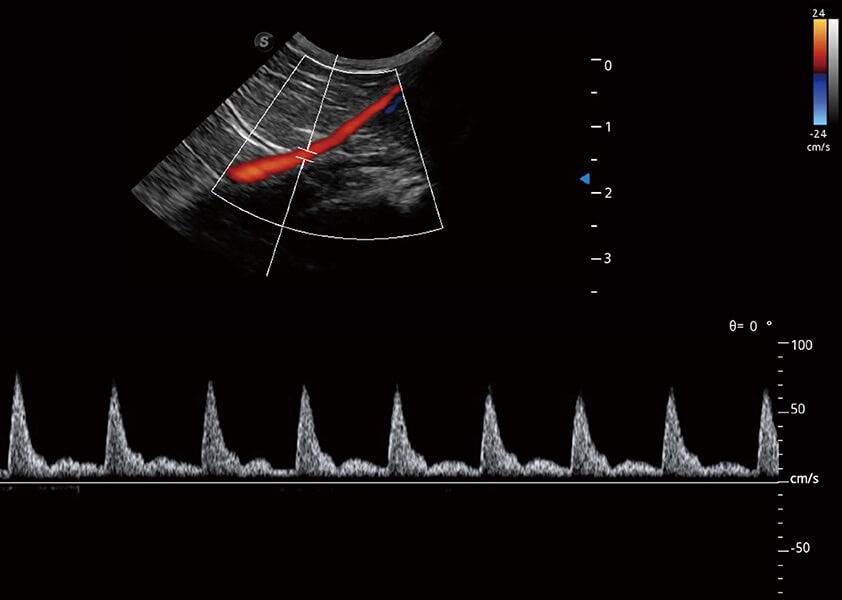

ProPet 60 作为一款高端台式动物超声设备,为动物医生的日常诊断提供了一系列贴合动物临床需求、解决临床实际问题的高级成像功能。凭借全系列高清探头,满足医生对腹部、心脏、生殖、浅表、肌骨等成像的所有需求,切实帮助您提升检查效率,提高诊断信心。

动物是人类最亲密的朋友和最值得信赖的伙伴。球速体育入口也一直致力于探索动物专用的超声影像解决方案。 全新推出的ProPet系列,是球速体育入口在动物超声影像智能化、专业化、精准化的一次跨越式革新。动物不能用言语来表述自己的不适,通过超声影像,ProPet系列搭建了动物医生与不同物种沟通的“桥梁”,为动物医生注入了“治愈之力”。